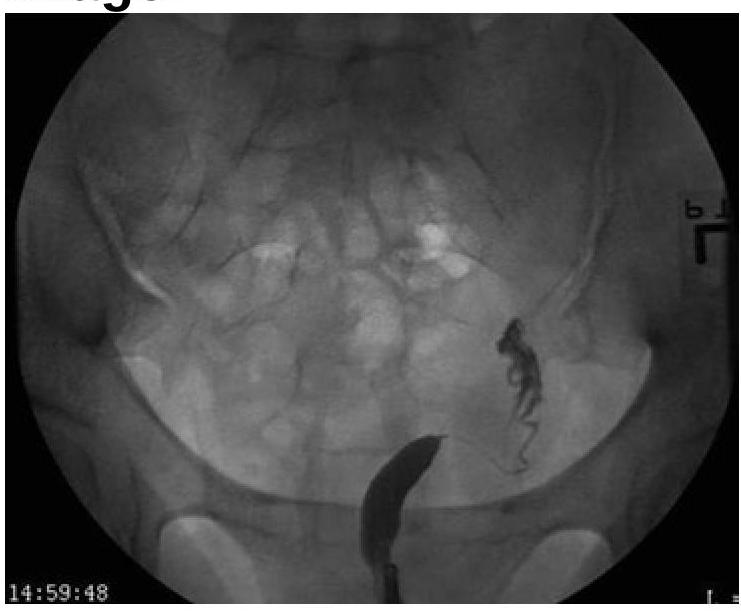

Explanation: ***Unicornuate Uterus*** - The image distinctly shows **only one fallopian tube and one rudimentary uterine horn** on the right side, indicating a unicornuate uterus. - This malformation results from the **incomplete development of one Müllerian duct**, leading to a single, banana-shaped uterine cavity. *Uterus didelphys* - This condition involves **two completely separate uteri**, each with its own cervix and vagina. - The image does not show evidence of two distinct uterine bodies or cervices. *Bicornuate Uterus* - A bicornuate uterus is characterized by **two uterine horns that fuse caudally**, creating a heart-shaped appearance with a shared cervix. - The image clearly lacks the characteristic heart shape and shows only one functional horn. *Septate uterus* - A septate uterus has a **fibrous or muscular septum** dividing the uterine cavity, while the external uterine contour remains normal. - The image does not show a septum or a normal external uterine contour with an internal division; instead, it presents with a single underdeveloped horn.